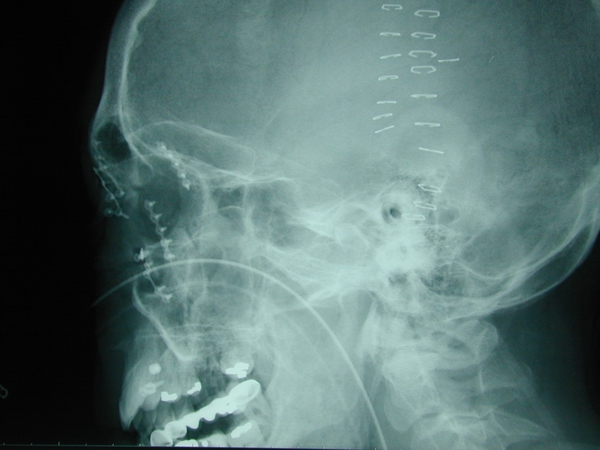

Patient 2

Multiple facial fractures